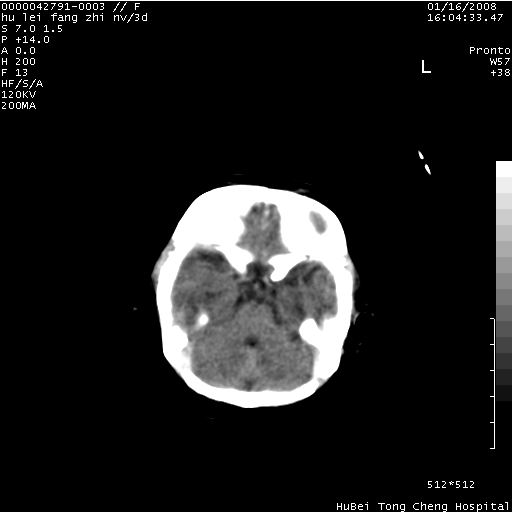

患儿 女,3天。惊跳,纳差。第二胎顺产,羊水ⅱ度。

临床诊断:hie?

颅脑ct轴位平扫(层厚、层距均为7mm),图像如下:

hie合并蛛网膜下腔出血

hie合并蛛网膜下腔出血,五、六脑室形成。

支持hie伴少量蛛血.

支持胼胝体发育不良。

支持hie,胼胝体发育差些

支持胼胝体发育不良